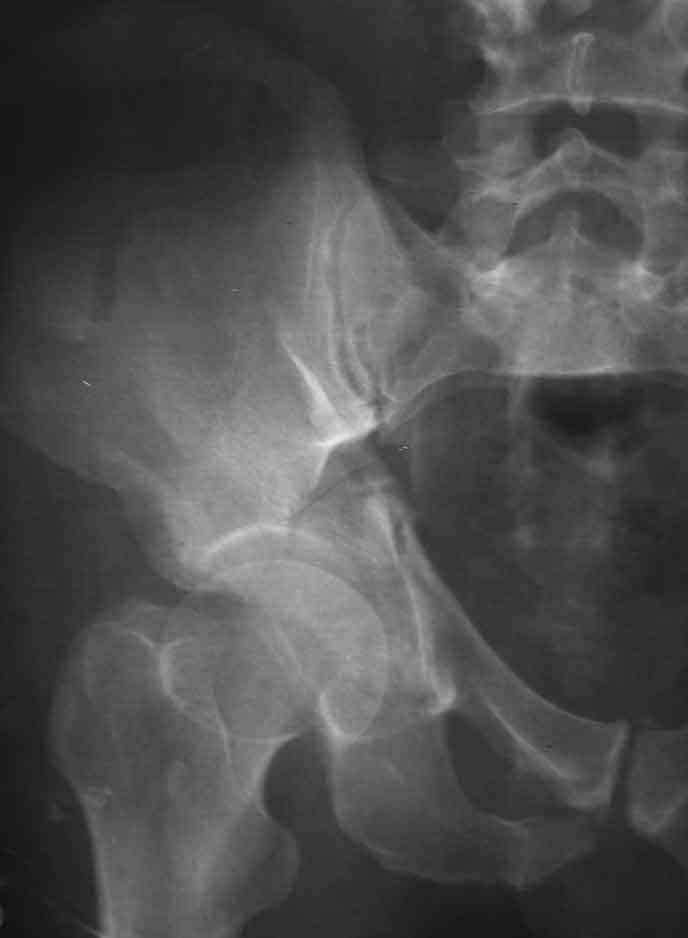

I am sending another iliac view, and a marked version of the AP I already sent. In this AP, the

proximal part of the greater sciatic notch as well as the distal parts of the ilioischial and iliopubic lines are marked with a grey interrupted line. A white interrupted line marks what could be an exit through the obturator foramen, or so I assume.